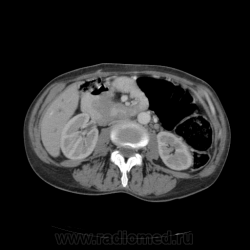

КТ ОБП - гепатомегалия, признаки панкреатита

МРТ ОБП - от 16.12.10 гепатомегалия, расширение панкреатических протоков.

Похоже на то, что все было списано на калькулезный холецистит. Наши морфологи пересмотрели стекла с гистологией и окончательно написали о наличие высокодефференцированной аденокарциноме. У меня только две мысли образования исходит из БДС или первичный рак 12п.к., хотя сейчас гадать бесполезно. 12п.к. циркулярно сужена.